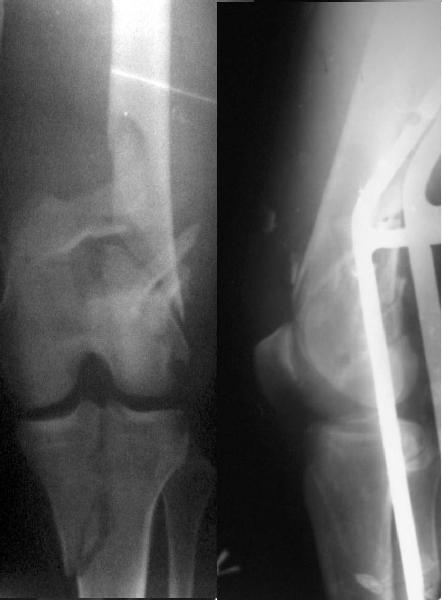

Re: Open supracondylar femur fx

And why LISS is superior here than nail?

Look what we would have done.

Zsolt Balogh 31 Октябрь 2004, 20:46

I would not say that the LISS is superior to the nail. If I would, I had not post original mail. I wanted to generate discussion. Your option is a very viable one. I feel a little bit shaky the distal femur, but it is just gut feeling no science behind it. Any way nice fixation, congarts!